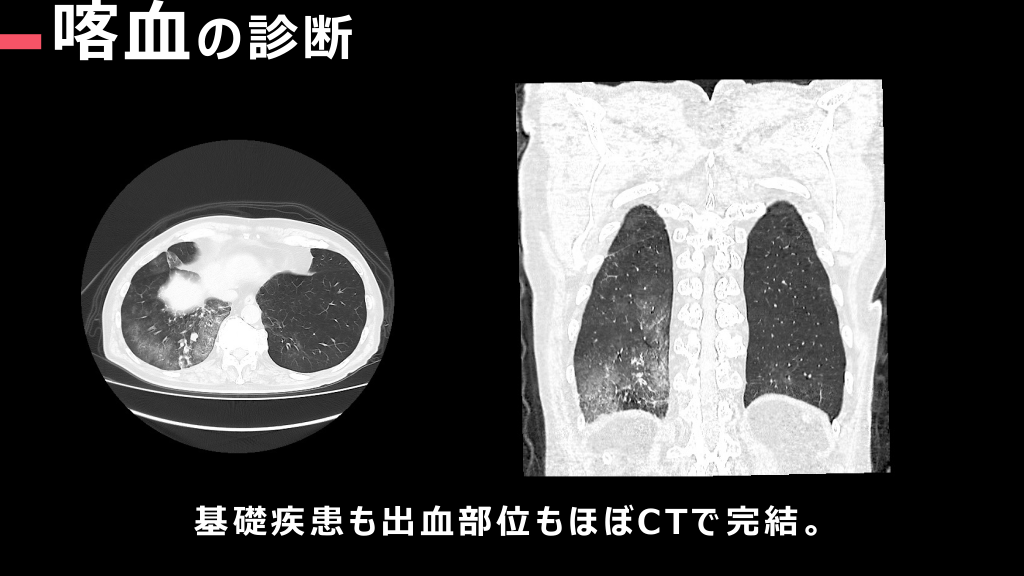

#6.

喀⾎ の診断 基礎疾患も出⾎部位もほぼCTで完結。